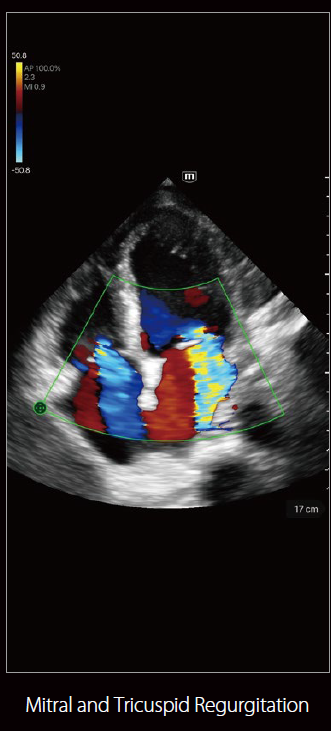

صور متعلقة